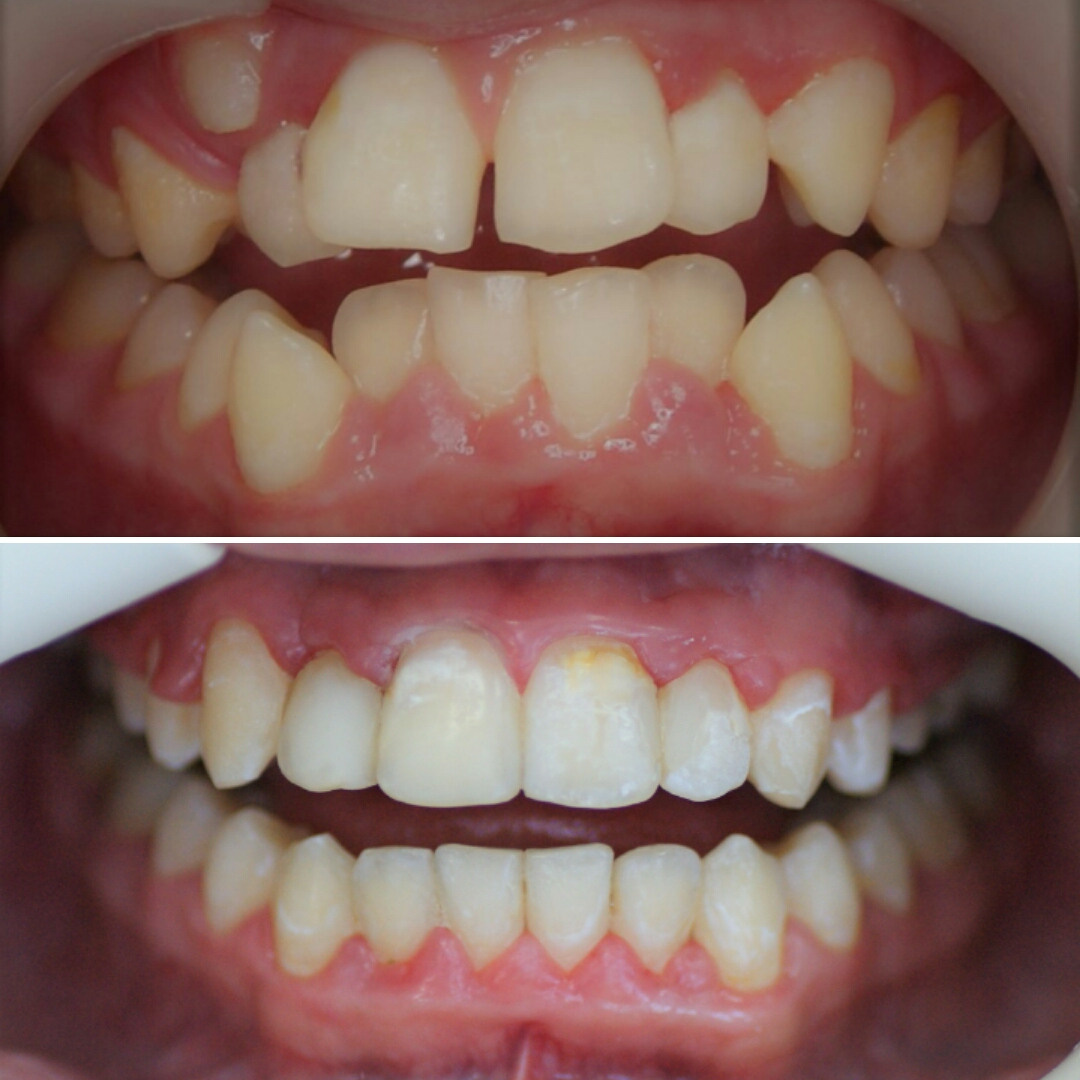

Большое путешествие зубов на своё законное место.

Эта фраза знакома многим ответственным родителям, которые привели на приём к ОРТОДОНТУ своего ребёнка в 5-10 лет, заподозрив проблему или понимая, что места постоянным зубам откровенно не хватает! Горькая правда в том, что брекеты - не волшебное средство от всех проблем, они "расставляют" зубы внутри сформированого объёма челюсти, но никак не влияют на её рост. Родители ждут, а тем временем драгоценное время, когда ребёнок растёт, уходит... Во взрослом возрасте приходится удалять здоровые зубы или прибегать к ортогнатической хирургической операции. 📸 На фото узкая нижняя челюсть, места постоянным зубам нет, боковые резцы прорезываются "вторым рядом".

❓Ну что? Будем ждать 12 лет? Или будем помогать ребёнку?

✅ Помогаем с помощью расширяющей дуги, пружины и зацепных элементов, которые зафиксированы на МОЛОЧНЫЕ зубы